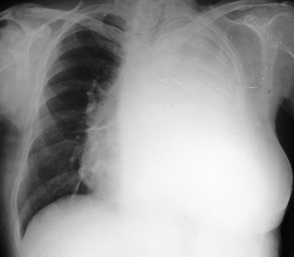

Rx toracică, incidență P-A

DESCRIERE:

la niv. întregului hemitorace drept → opacitate extinsă, nesistematizată, de intensitate mare, omogenă

caracter expansiv → împinge traheea și mediastinul de partea opusă

diafragm deplasat în jos

lărgirea spațiilor intercostale

umplerea spațiului costo-diafragmatic

DX: pleurezie masivă

DD: atelectazie → caracter retractil